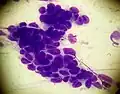

A cluster of basaloid cells on a smear taken from a patient with basal cell carcinoma (May-Grünwald Giemsa x1000).

A cluster of basaloid cells on a smear taken from a patient with basal cell carcinoma (May-Grünwald Giemsa x1000).